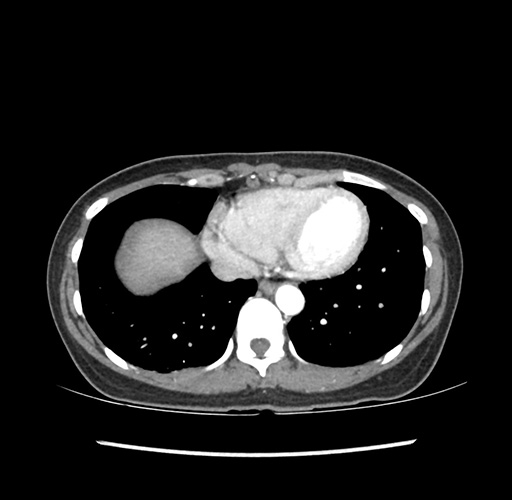

Imaging Analysis

Look through the patient's CT scan to identify any areas of concern for the necessary procedure.

Based on your CT findings, which issue(s) would give reason for "planned slowing down moment(s)" in this case?

Considering a standard left lateral sectionectomy procedure, what step(s) of the operation would you do differently in this case ?